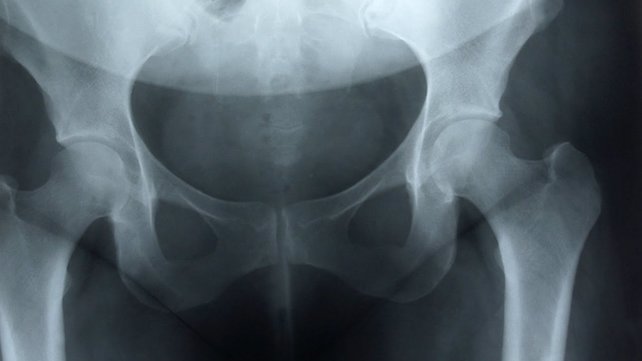

Hip Conditions

The division of pediatric orthopedics treats hip problems, including hip dysplasia and Legg-Perthes disease.

Developmental hip dysplasia occurs when the hip joint doesn’t develop normally, and the ball of the femur (thigh bone) is loose or completely out of the socket. Symptoms include a leg that appears shorter, is turned outward, or looks otherwise abnormal compared to the other leg. Untreated, the condition may cause pain and result in osteoarthritis.

Legg-Perthes disease is a condition in which blood flow to the hip joint is cut off, resulting in bone damage that causes the hip joint to become painful and stiff. Femoroacetabular impingement results from abnormal contact between the ball of the femur and the outside of the hip socket. Over time, the hip joint can become damaged through repeated motion of the hip, especially during strenuous or sustained activity.